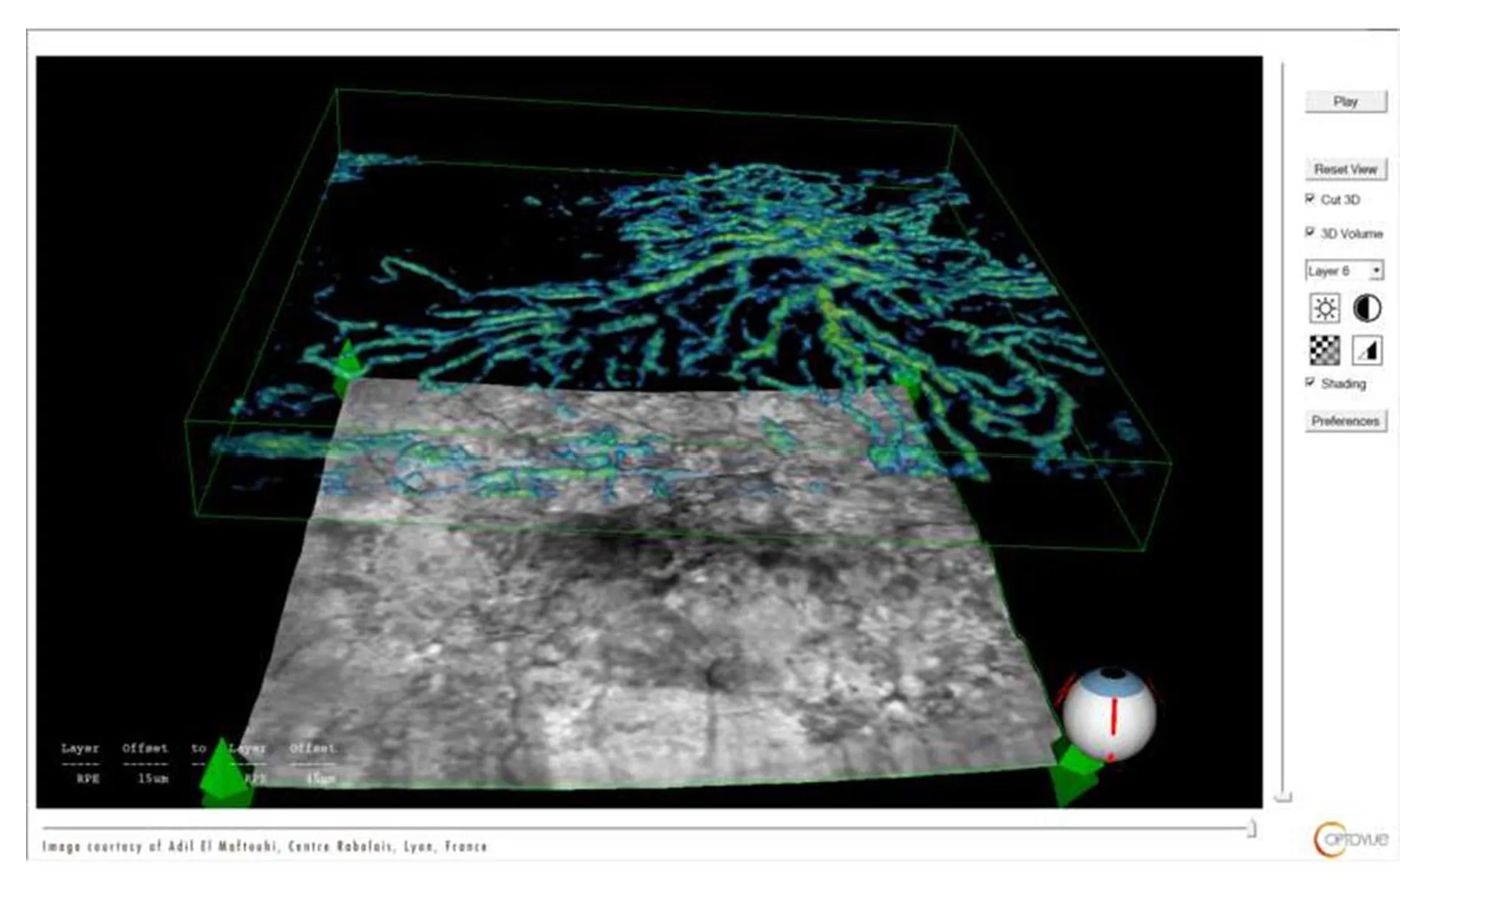

Оптический когерентный томограф Optovue Solix обладает повышенной скоростью сканирования — 120 000 А-сканов в секунду. SOLIX предоставляет множество инструментов для нового поколения борьбы с заболеваниями, которые повышают пропускную способность и обеспечивают превосходный уход за пациентами. В отличие от томографов более ранних поколений ОКТ SOLIX OPTOVUЕ может определять наличие конкрементов и новообразований сосудов сетчатки и хориоидеи, позволяет получать максимально точную послойную визуализацию структур глаза.

- Диапазон сканирования в режиме ангио-ОКТ — от 3х3 до 18х18 мм;

- Программа AngioAnaliticsTM для количественного анализа сосудов сетчатки;